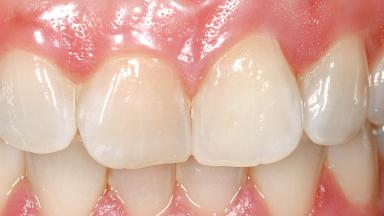

A 29-year-old female patient presented for treatment to replace the upper left central incisor tooth with an implant- supported restoration. The tooth had been intermittently symptomatic for the previous 12 months. The tooth had originally suffered trauma about 15 years previously. Several endodontic treatments had been performed, including an apicectomy procedure to retain the tooth. The patient was healthy and a non-smoker. She had reasonable expectations in regard to esthetic outcomes and the risk of marginal tissue recession following treatment. At medium smile, the gingival margins of the upper teeth were visible, with a display of 3 to 4 mm of the gingival margins. Gingival recession of tooth 21 and a discrepancy in the gingival levels between teeth 11 and 21 was observable during normal speech and smile.

Soft Tissue Contour and Volume | Slightly compromised |